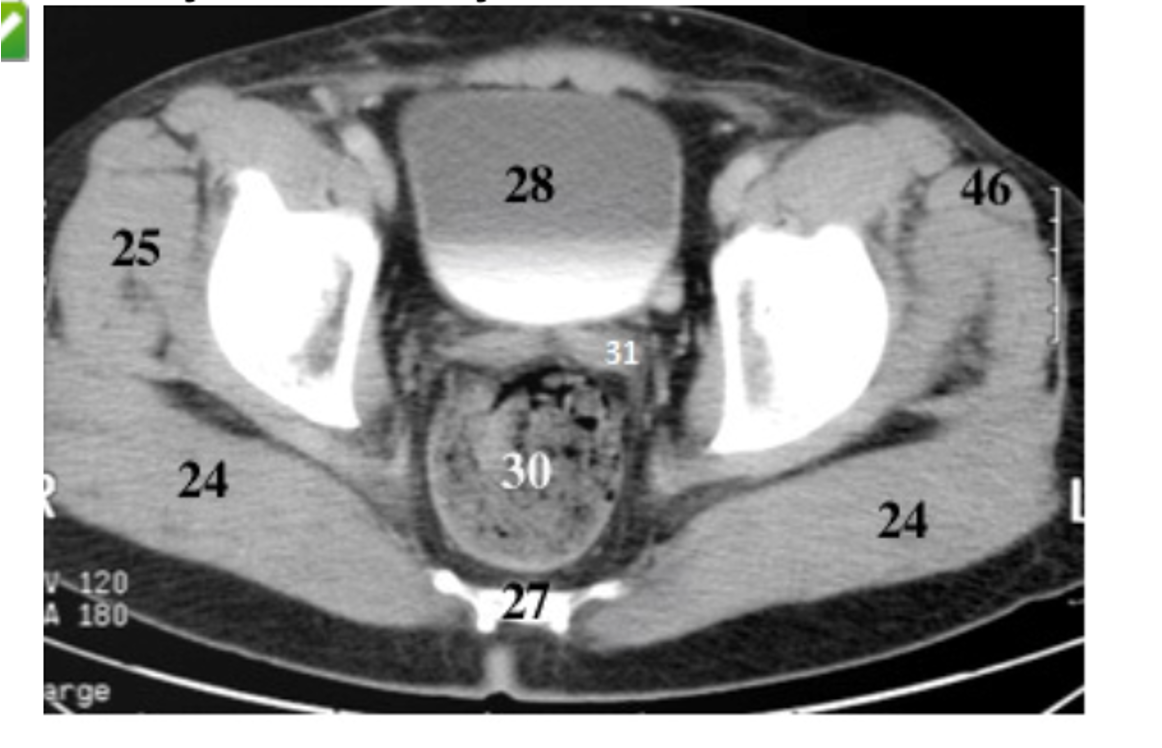

29

pubis

30

ishium

rectum

28

bladder

31

seminal vesicles